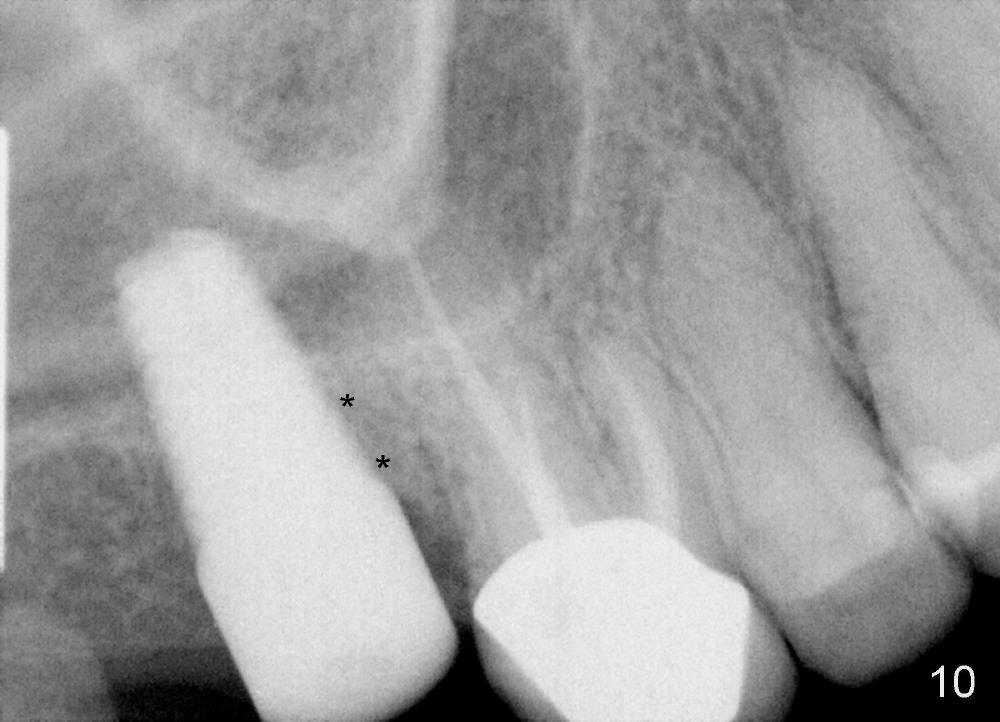

Fig.10 shows the implant 5.5 months postop with apparently bone growth in the former mesiobuccal socket (*). The implant is stable with healthy gingiva around it.